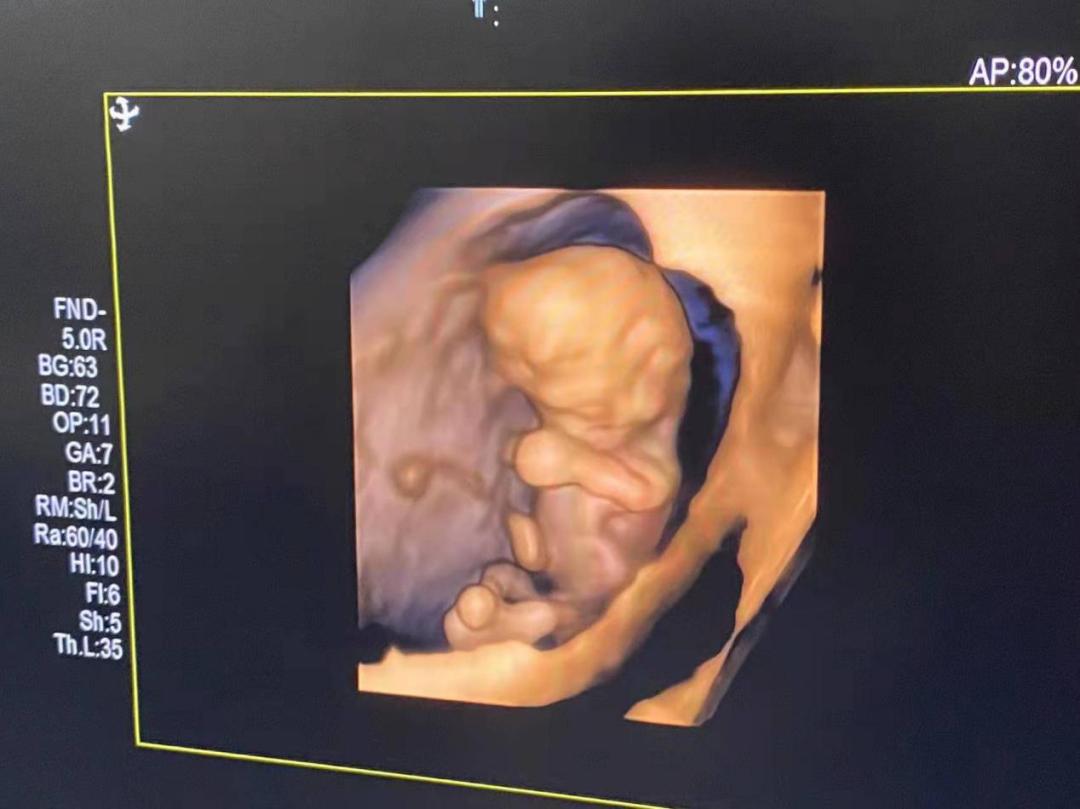

知道木木是在孕10周+的时候了,后悔没有早点知道木木,走了不少的弯路,跑了好多家医院,每天都在担心胚胎发育不好,犹记得第一次面诊木木的时候,他说我其他还好,就是血小板数值高,有高凝的风险,马上告诉我别太担心,遵医嘱用药,会没事的,给了我莫大的信心。让我把肝素每天一支,阿司匹林每天100mg用上,定期产检,按时复查就可以了,于是我就跟着木木的方案开始用药,知道肝素、阿司匹林是专门针对凝血方面疾病的,我安心了很多,超声NT宝宝都是爱你的形状。